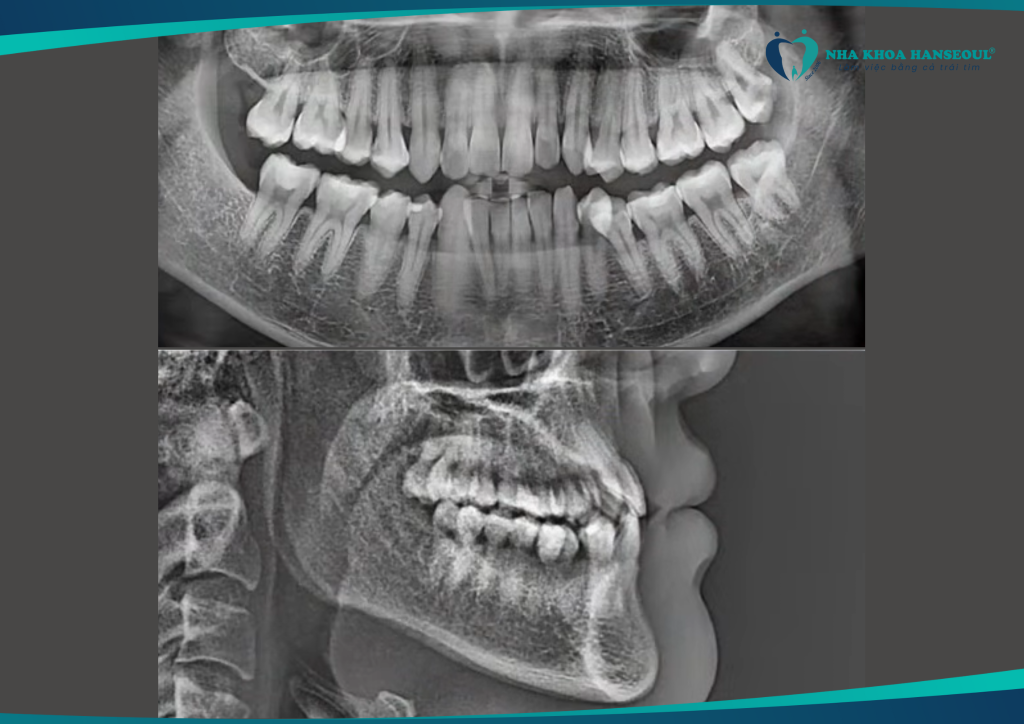

Khớp cắn ngược hạng III thay đổi ngoạn mục với Invisalign tại Hanseoul